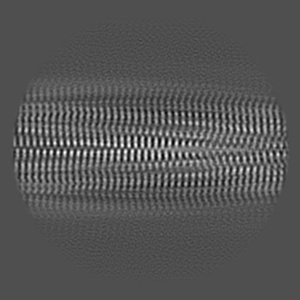

Type1 alpha-synuclein filament assembled in vitro by wild-type and mutant (7 residues insertion) protein

Helical reconstruction2.7 Å

Sample: Alpha-synuclein filament assembled in vitro by wild-type and mutant (7 residues insertion) protein